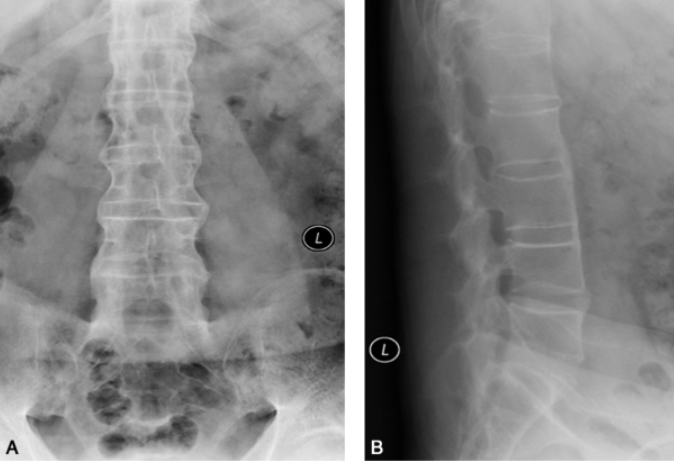

图2 腰椎强直性脊柱炎男,52岁。A、B.腰椎正侧位片显示骶髂关节骨性融合,腰椎体成方椎,椎间小关节面模糊、硬化和增生。

受累在骶髂关节之后,由下脊椎开始,逐渐向上发展。椎体前角表面骨质吸收,导致正常椎体前缘凹陷消失,椎体变成方形呈所谓的“方椎”,椎间小关节面模糊、硬化和增生。骨质可有明显疏松。3%~28%的患者有脊椎间隙变窄和邻间盘椎体骨质破坏、周围多伴有骨质硬化。椎间纤维环、椎间小关节囊、前纵韧带、后纵韧带、黄韧带、棘上韧带和棘间韧带可发生不同程度骨化。椎间纤维环外层骨化,使椎体彼此相连,正位像脊柱呈竹节状。棘间韧带、棘上韧带和两侧椎间小关节囊骨化,形成三条致密纵带,颇具特征(图2)。晚期,脊柱变直,均匀后突或合并侧弯畸形。少数颈椎受累出现寰枢关节半脱位并在半脱位基础上发生融合,合并蛛网膜囊肿者可有腰骶部椎管扩大。

早期椎间小关节面毛糙不整,继而出现小的关节面下骨质侵蚀并伴有硬化,晚期主要发生肥大增生,关节囊及黄韧带肥厚骨化。